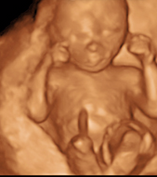

ECOGRAFIA 4D

ECOGRAFÍA 4D y 5D equipo lider ecografía

Ecografía 3D,4D Y 5 D